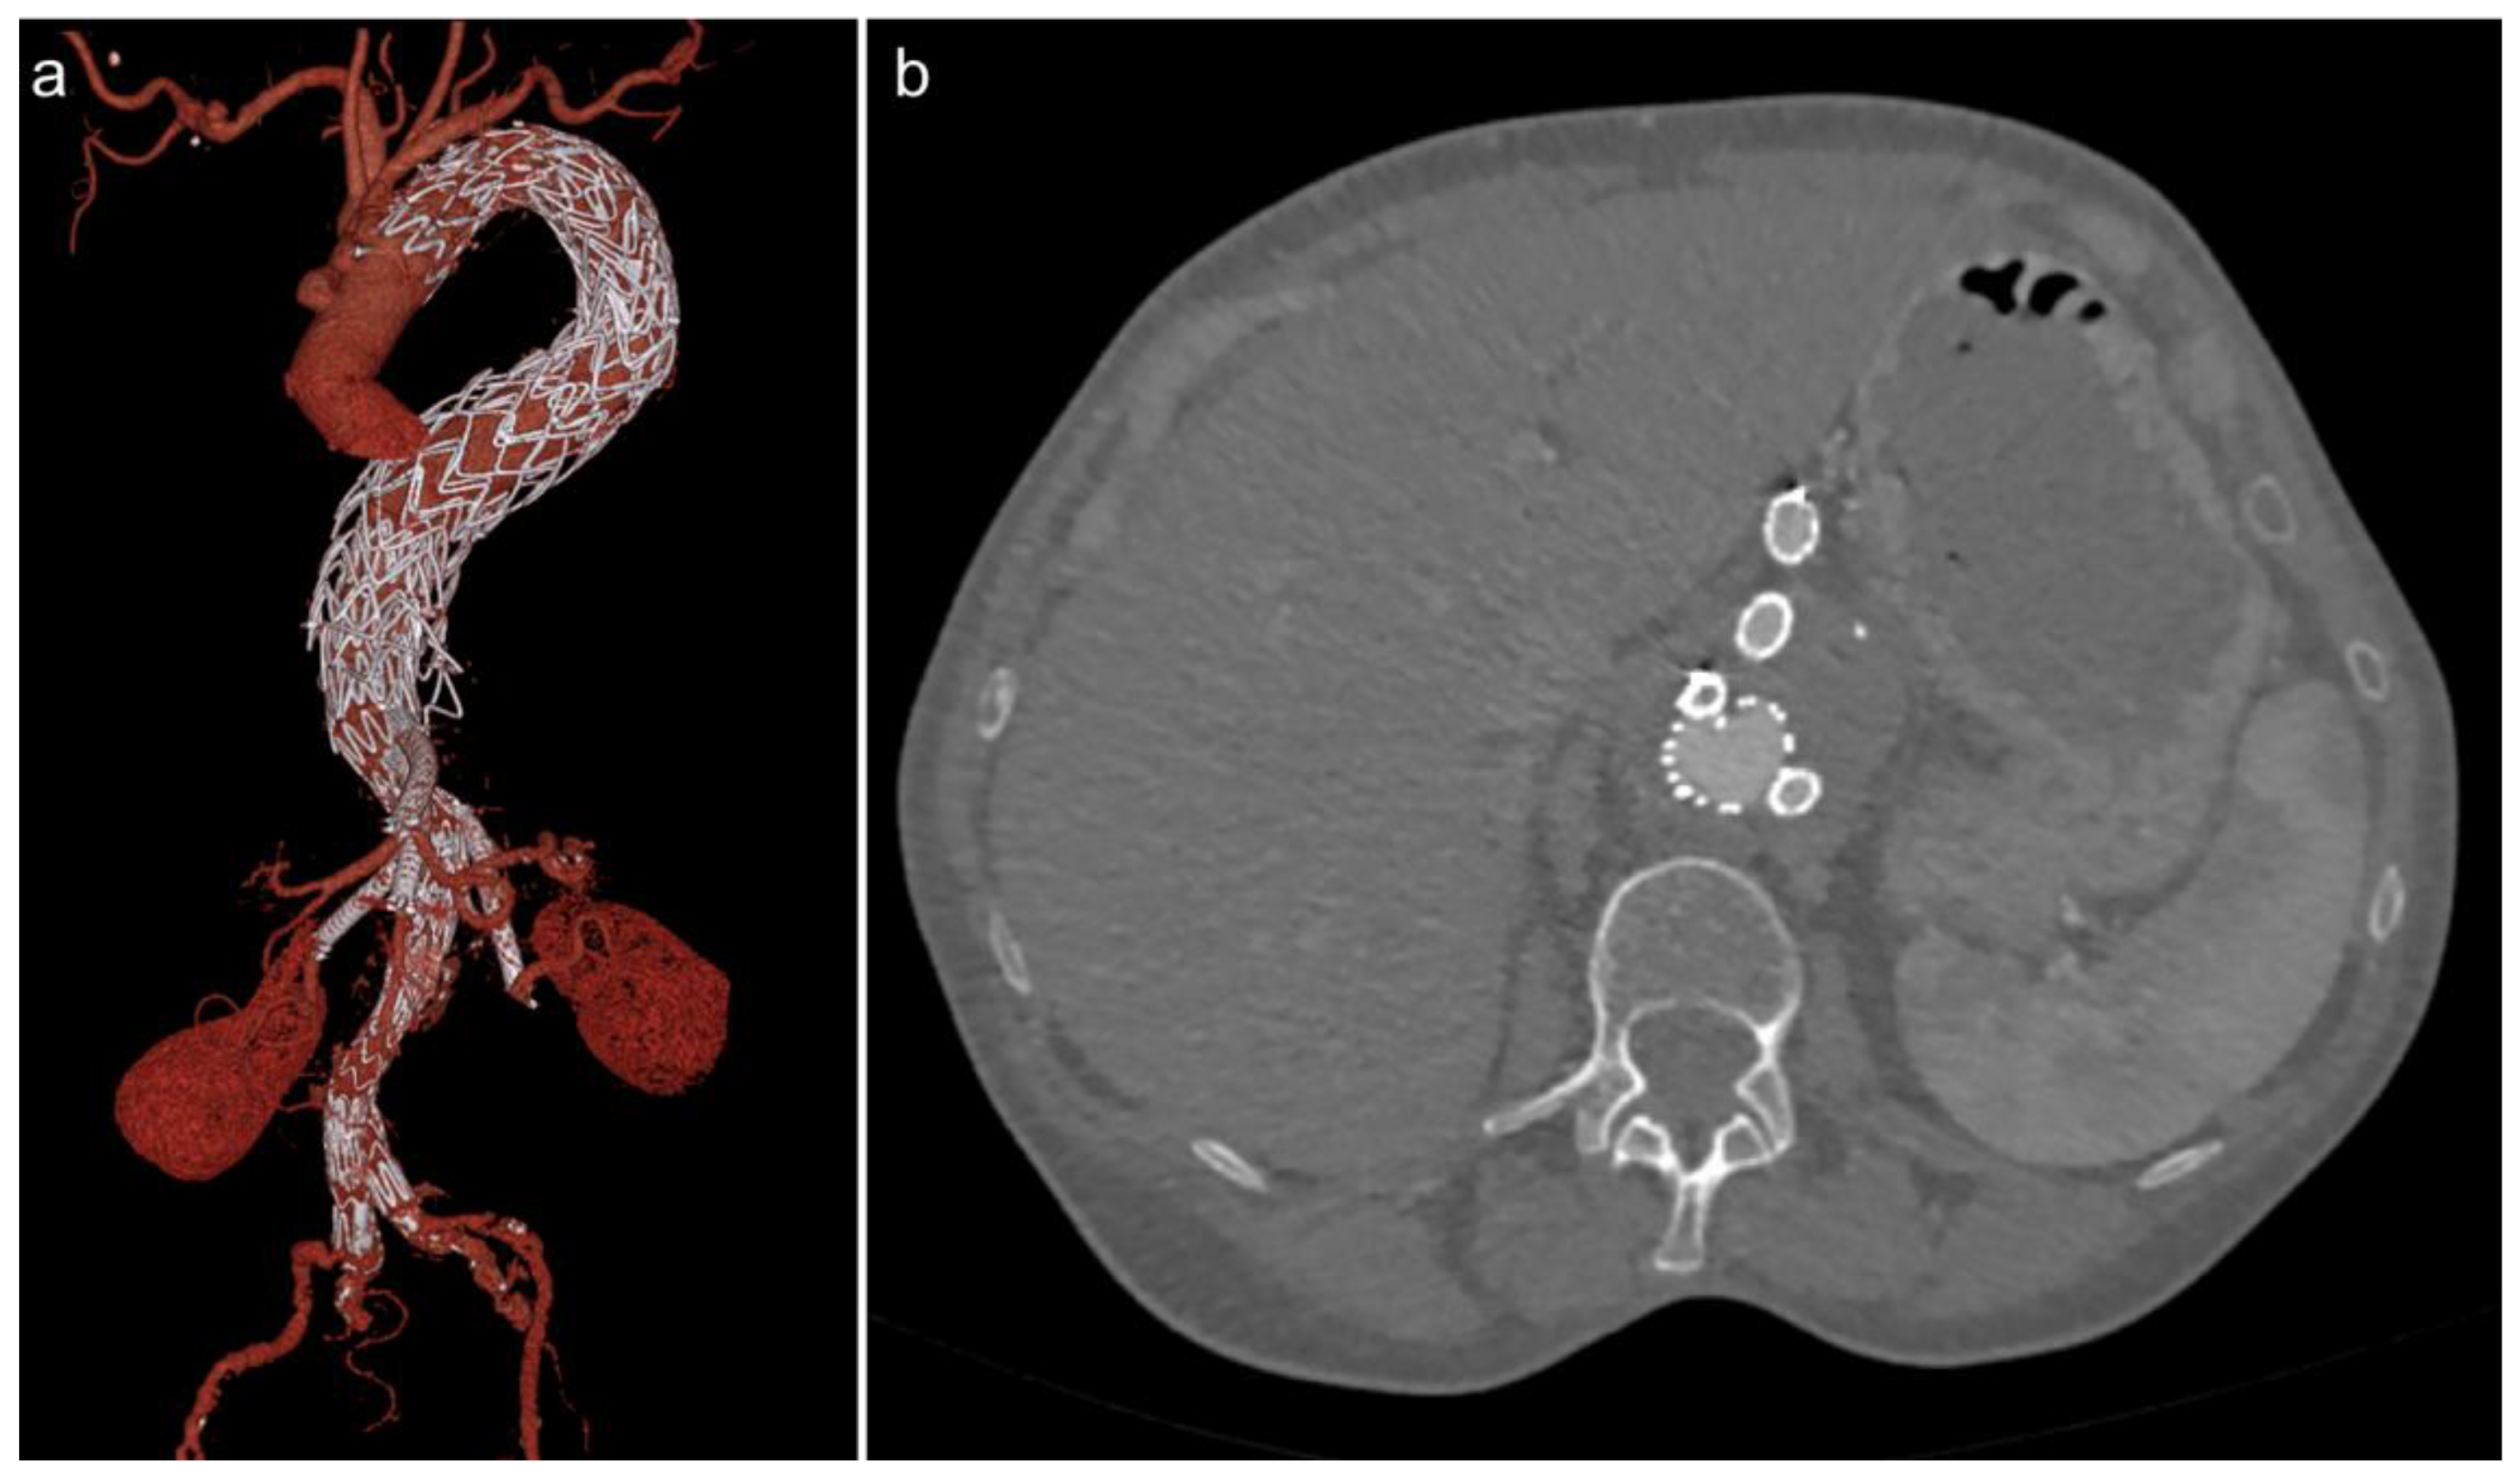

3.2. Fenestrated/Branched EVAR (FEVAR/BEVAR)

3.3. Endoanchors